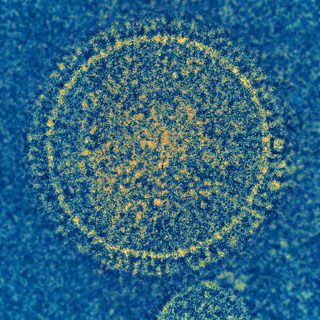

Virus sincitial respiratorio

Foto: NIAID